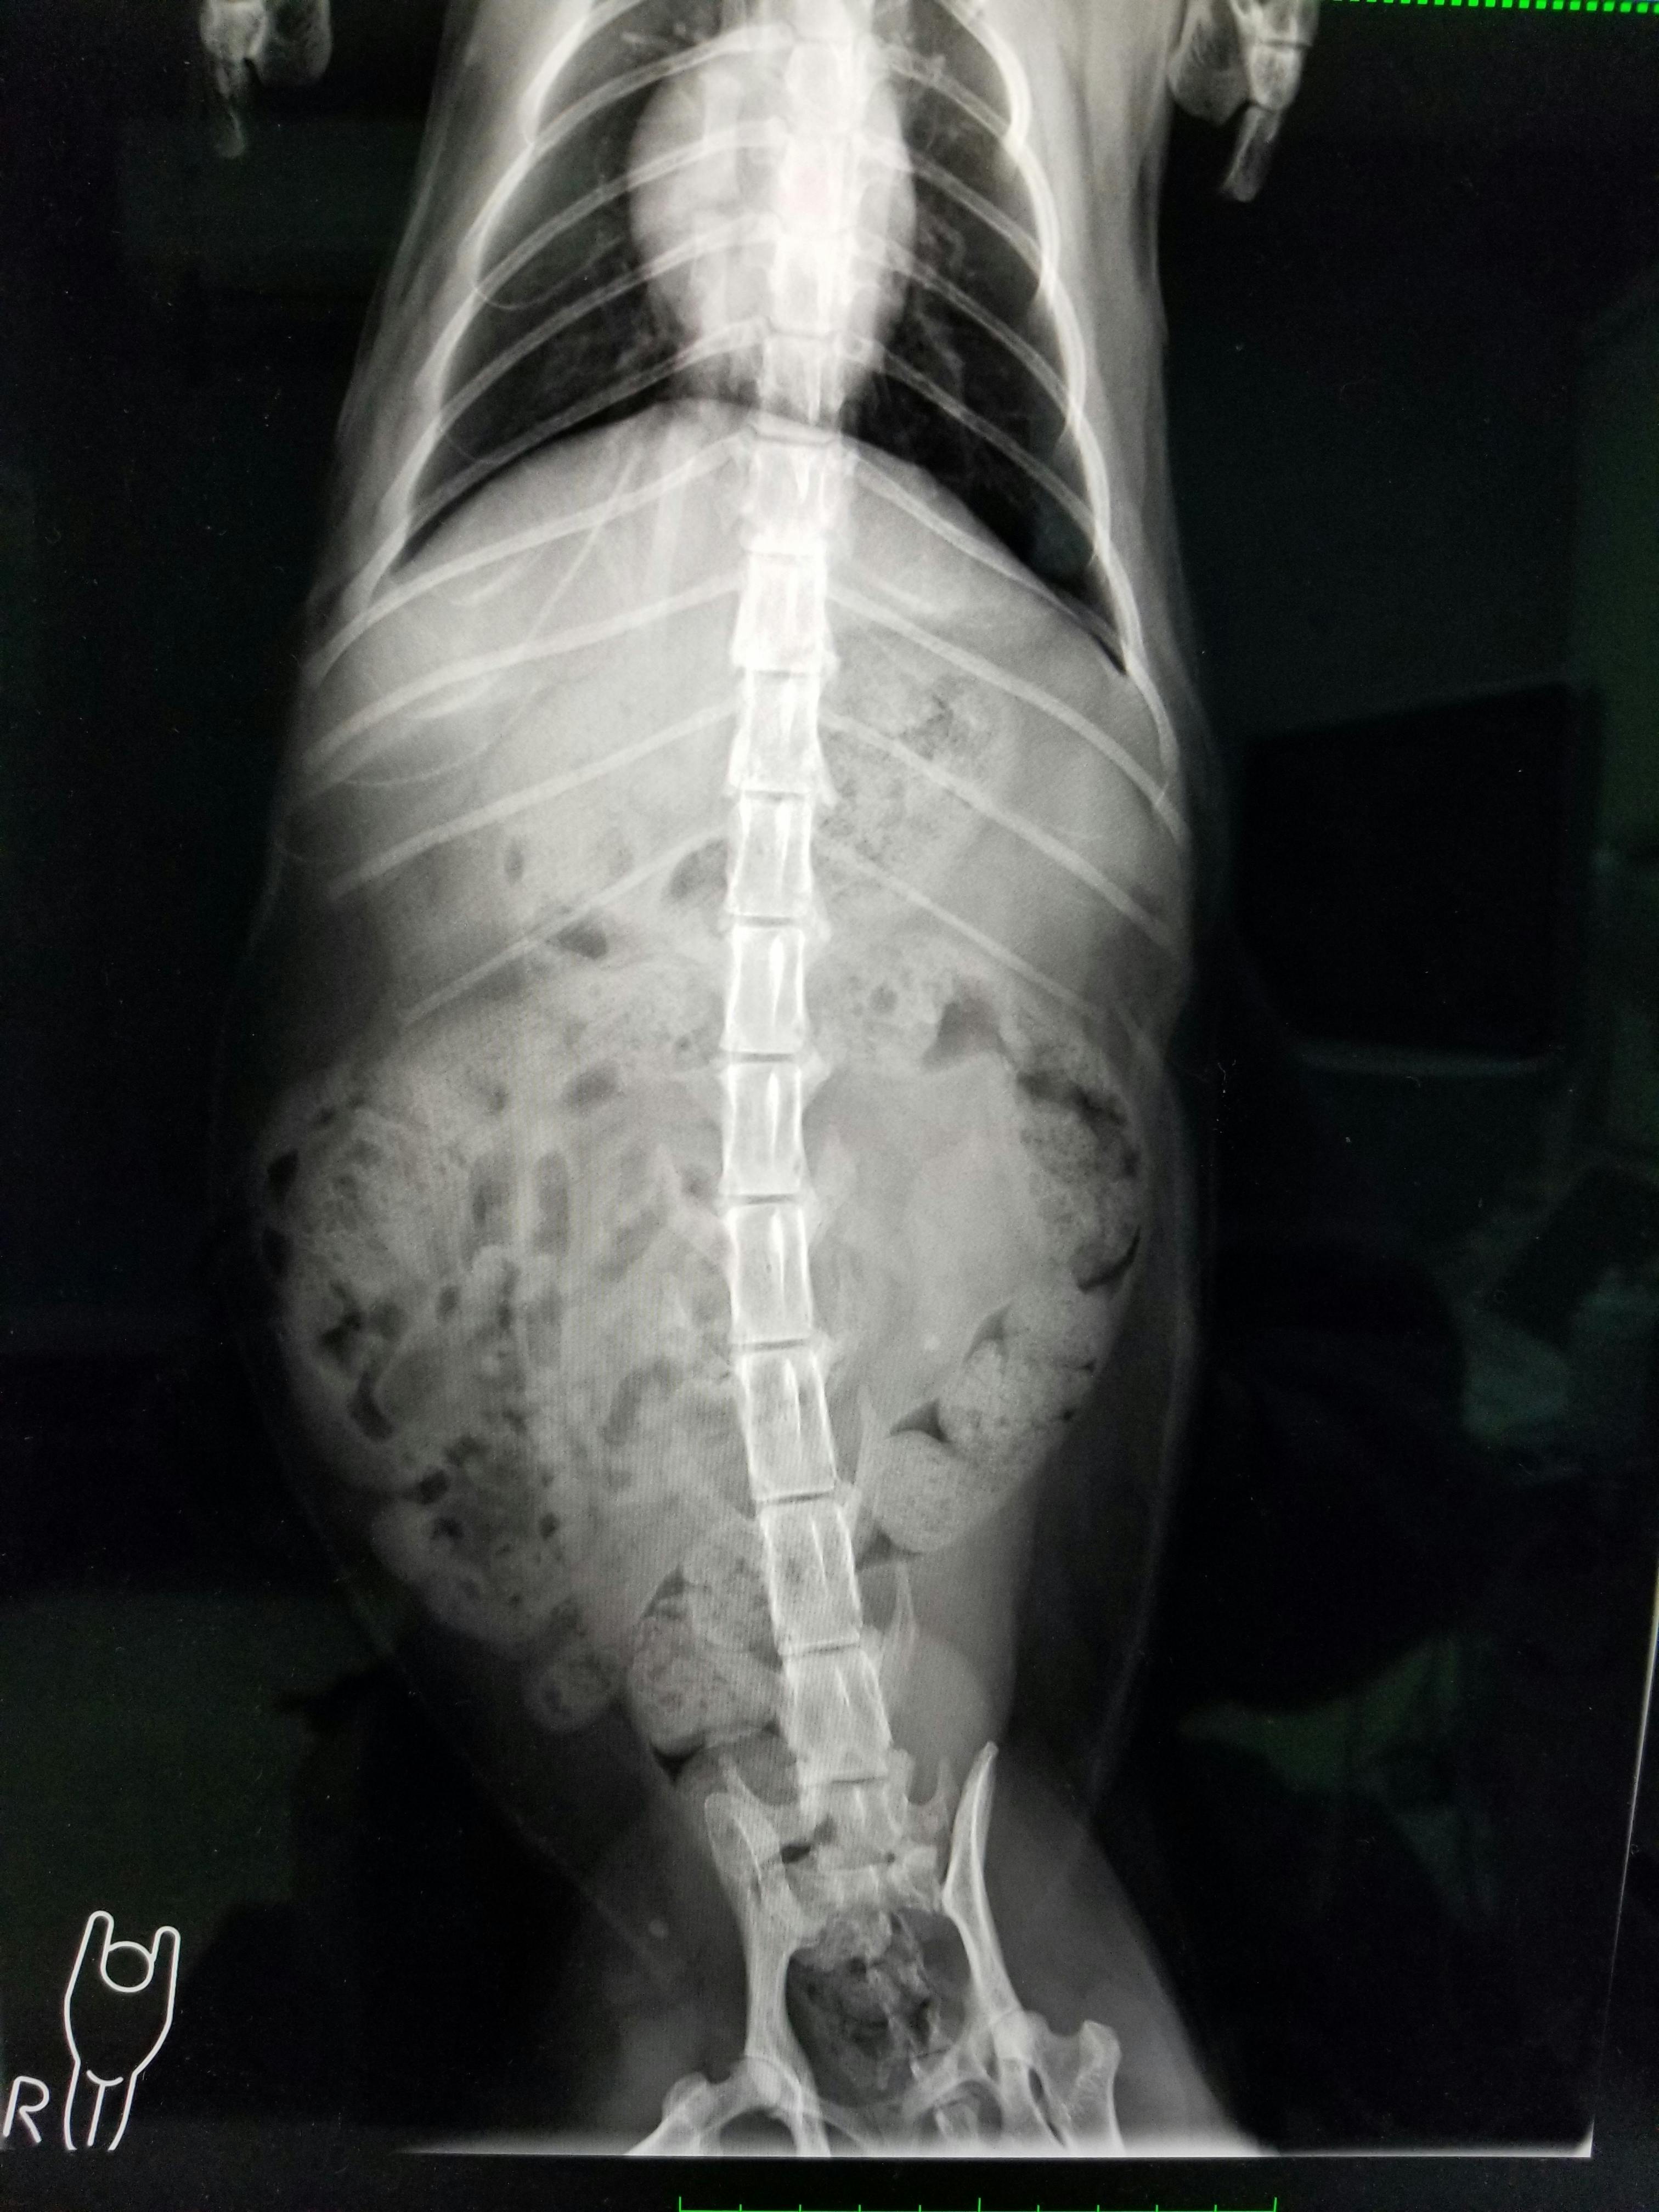

巨大結腸症により内科治療を行いました。

現在は高線維の食事に変更することで症状は抑えられています。

FIP(猫伝染性腹膜炎)です。発症から死に至ってしまうまでの期間は、最悪の場合、わずか平均9日間といわれ、年間で約1,000頭以上の猫ちゃんが苦しんでいると聞きました。

治すのには多額のお金が必要となり、飼い主さんからこれ以上はお金を出せないと相談されたため、保護しました。

現在も治療中で、感染症のため隔離されている状態です。